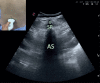

Ultrasonography has gained popularity in recent years among anaesthesiologists and being used widely for regional blocks and central venous catheterization. Ultrasonography for neuraxial blocks was found beneficial especially for determining the correct needle insertion site and estimating the needle insertion depth of epidural space. In many recent studies, ultrasound guided epidural and spinal blocks have been evaluated among obstetric patients. Pre-procedural lumbar ultrasonography and real time ultrasound guidance for neuraxial blocks was the subject of these studies. We aimed to evaluate lumbar ultrasonography for obstetric neuraxial blocks. We describe the principles of lumbar ultrasound scanning techniques and present a practical review of lumbar sonoanatomy. We discuss the potential impact and benefits of the ultrasound-guided technique in improving obstetric neuraxial blocks and limitations of its use in clinical practice, based on previous studies.